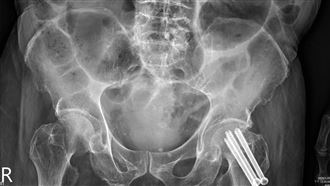

而醫師進一步詢問生活狀況,得知該名女病患平時生活很壓抑,除了養育孩子的重擔落在身上外,和丈夫的感情也不好,後來醫師替患者照X光,發現肺部疑似出問題,進一步進行低劑量電腦斷層檢查,才得知她竟罹患肺腺癌。